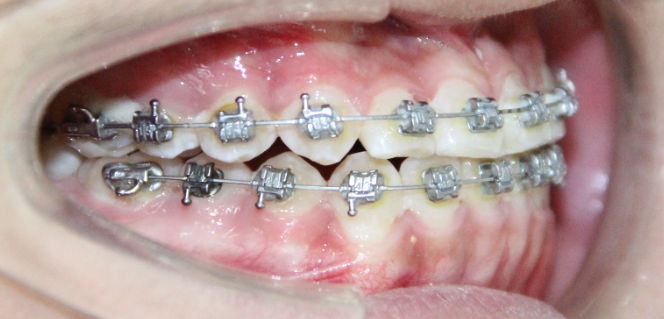

病例3

治疗前

治疗后